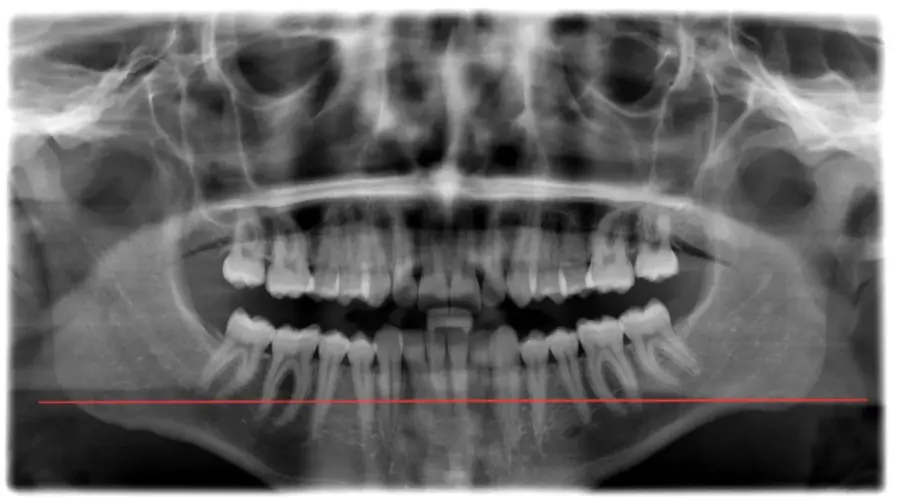

I’m 15.5 with noticeable jaw asymmetry - right ramus is longer than left and a slightly recessed lower jaw. My orthodontist said the it is skeletal and IF i want to correct it i may need jaw surgery (probably a bsso + genio) , but I haven’t been to a maxillofacial surgeon yet since i am 15 and my ortho said that there is no reason to go since they my jaw will still grow.

Even though it doesnt look that bad in xrays in my opinion the assymetry is noticeable and bsso would benefit me, becouse of my pretty short ramus (atleast it apears so on my left side) and mandible reccession